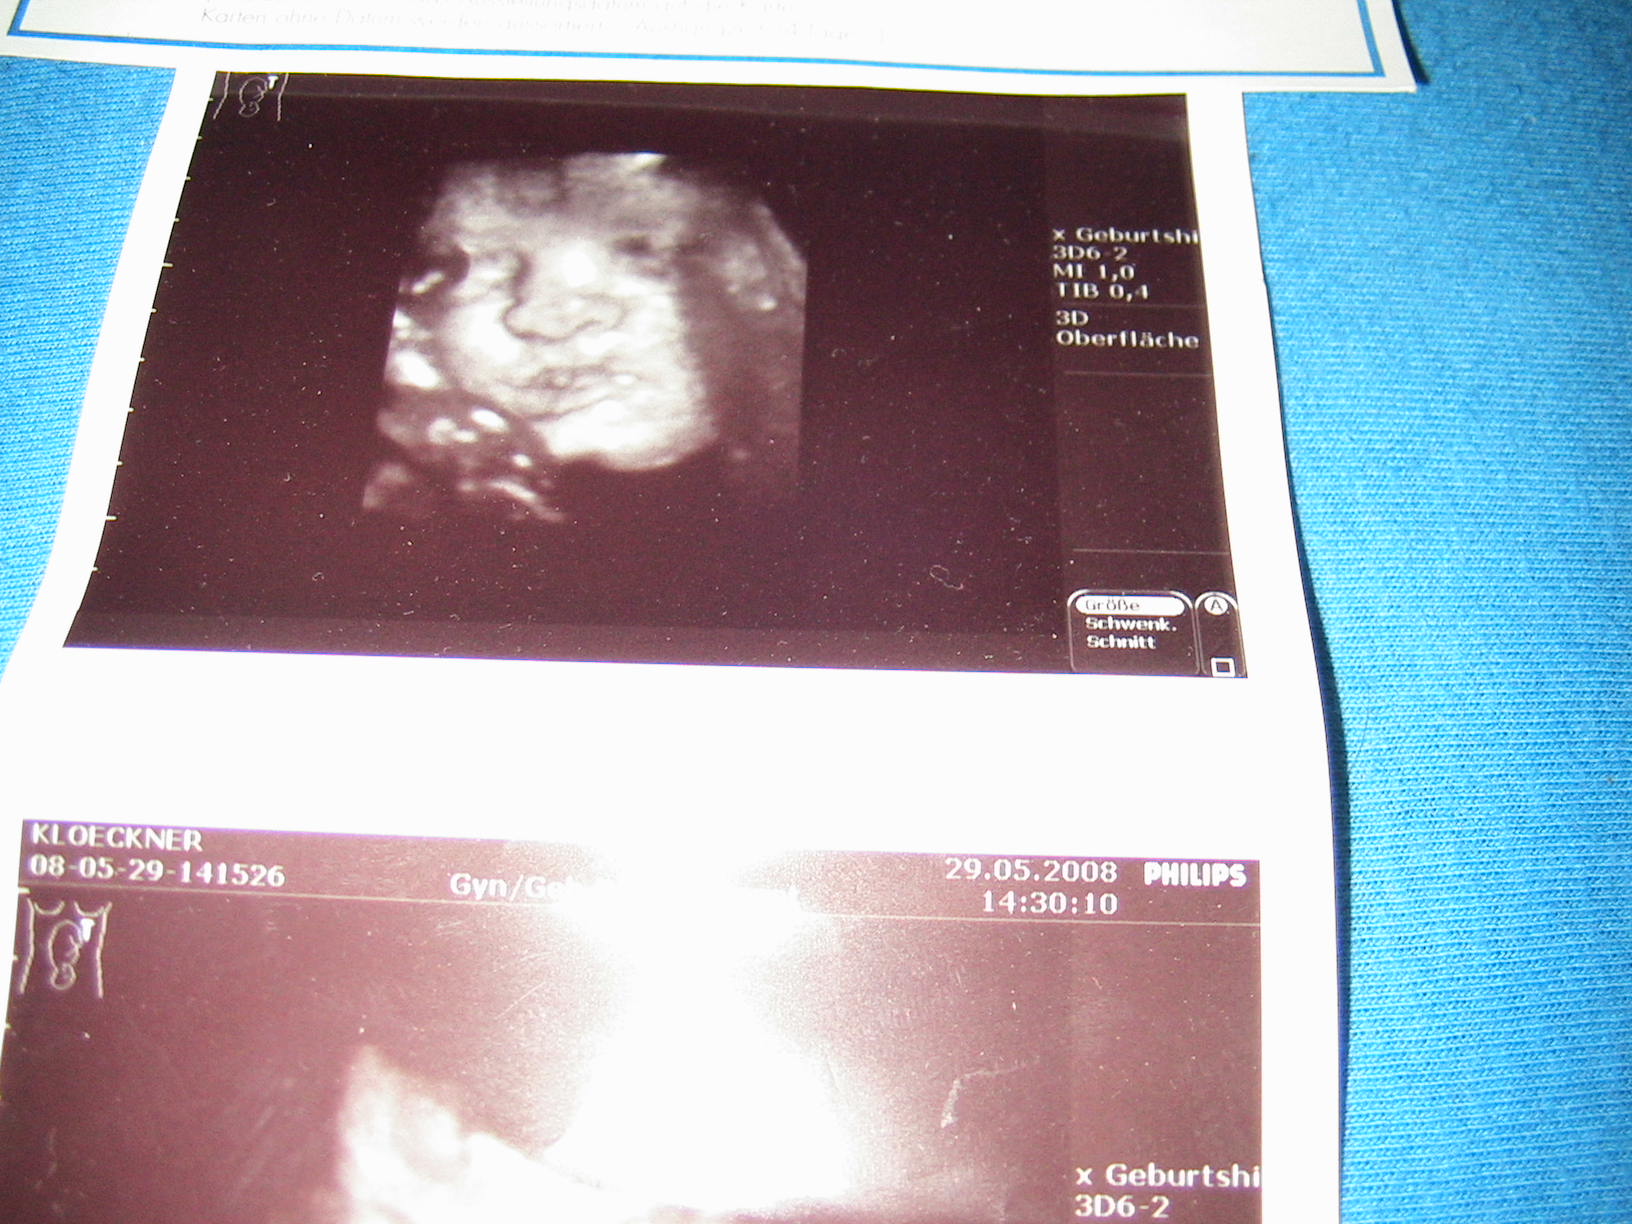

Bea,schön das du wieder da bist,im Krankenhaus musste ich liegen und bekamm Magnesium Infusionen und jeeden Tag 2mal ctg die Ärzte meinten das er schwer Aktiv ist oh oh mal gespannt wenn er auf der welt ist habe auch schöne bilder bekommen werde sie die die Tage mal einstellen.

Nadja, die Bilder sind echt der Wahnsinn man sieht alles so genau - unfassbar - gabs zu meiner Zeit noch nicht. Tja ich bin damals fast geplatzt vor lauter Spannung wie mein Mädele den aussehen wird........ und du weißt es schon. Echt ein süsser Fratz, freue mich schon auf die Original-Fotos. Hoffe du hast einen guten Foto.